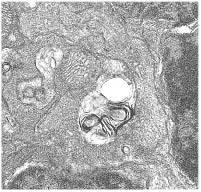

Una investigación pionera contribuirá a mejorar el conocimiento de las enfermedades minoritarias mitocondriales